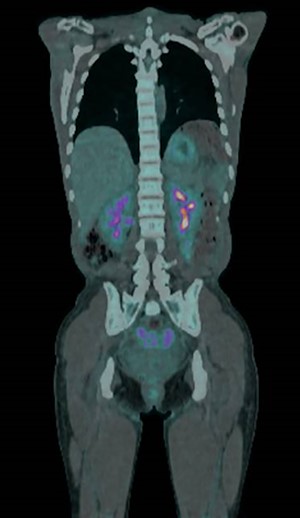

A positron emission tomography-CT (PET-CT) scan demonstrated abnormal tracer uptake in the omentum, right lower abdomen quadrant and pouch of Douglas (Fig. 2). A subsequent diagnostic laparoscopy for targeted biopsies however yielded only inflammatory changes with no signs of malignant processes. Post-operatively, the ascites resolved spontaneously, and on out-patient review at 4 weeks repeat blood tests and all clinical parameters had returned to normal.